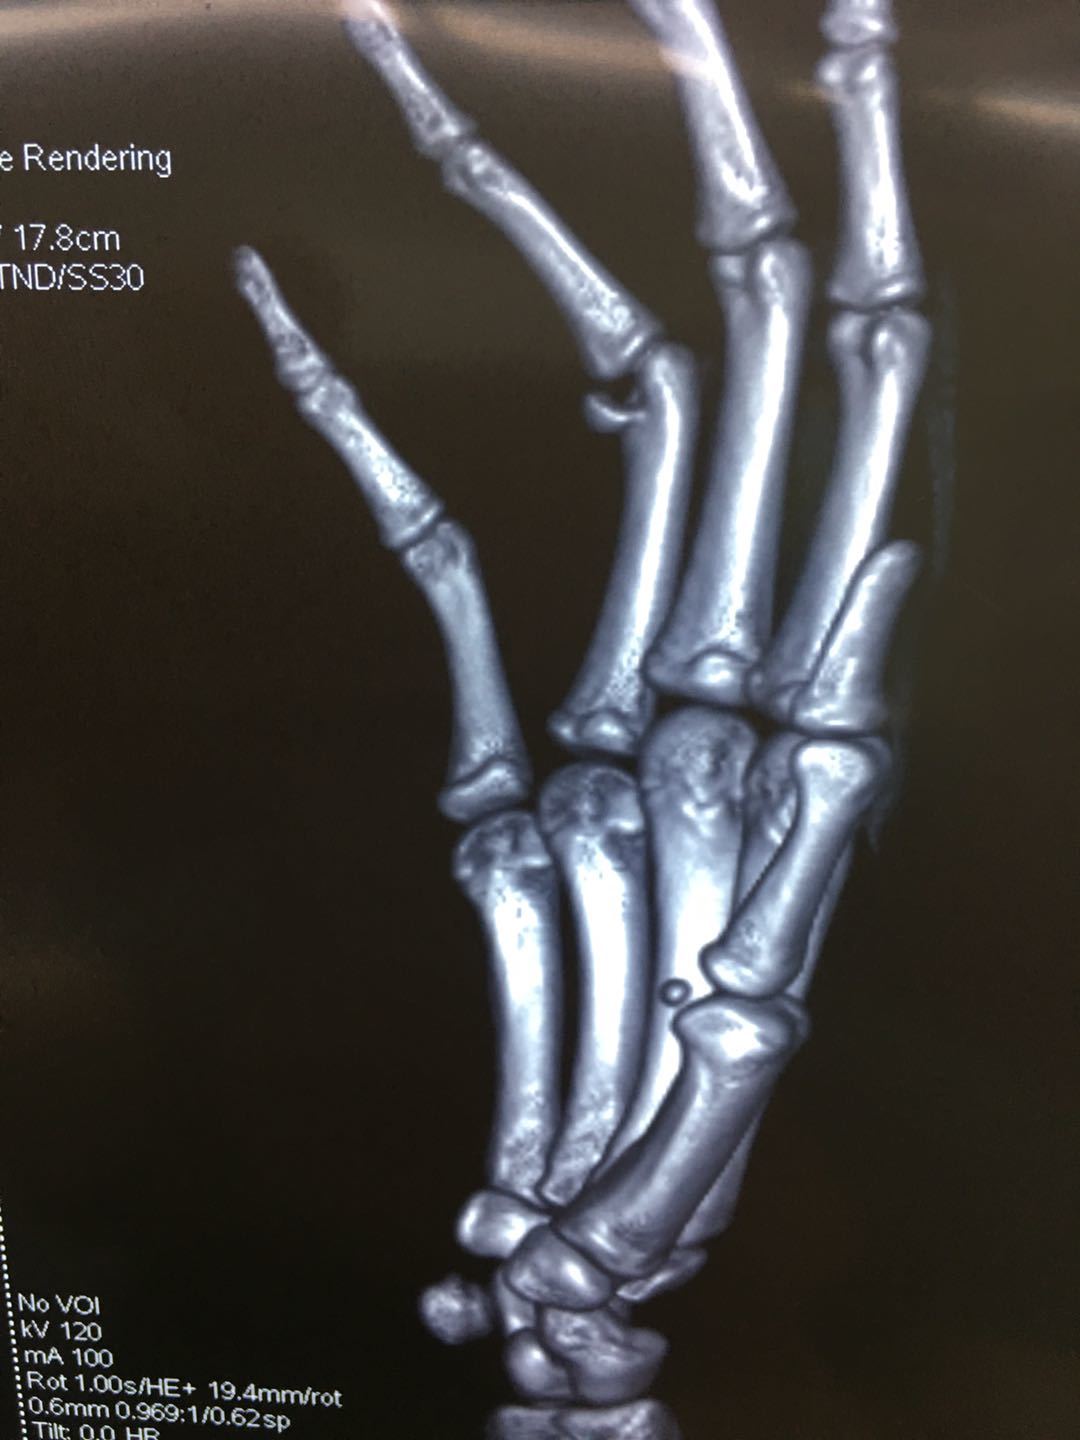

"手指近节远端hoffa骨折"一例报告 - 好大夫在线

图片尺寸1080x1440